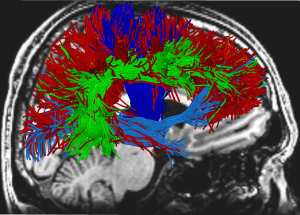

The image I found, below, is generated by one of the latest diagnostic tools, Diffuse Tensor Imaging, or DTI (see #6, below).

6. There is a new type of MRI called Diffusion Tensor Imaging (DTI) that is promising for seeing the neurological damage caused by TBIs in ways no other diagnostics are currently able to do. This will also aid in detecting where an injured person is in their recovery.

image from http://www.adlergiersch.com, “Advances in Neuroimaging in Detecting Brain Abnormality in ‘Mild’ Traumatic Brain Injury”